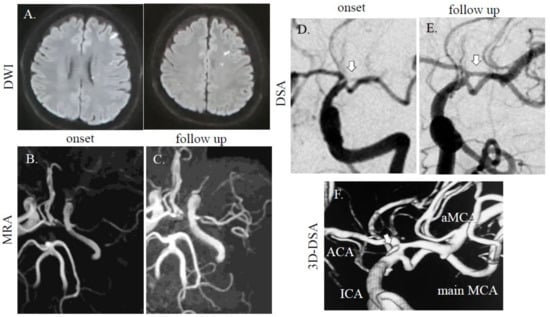

A healthy 56-year-old Asian man without vascular risk factors suddenly developed left body dysesthesia and walking difficulty at midnight. He had no history of collagen disorders. On arrival to the emergency room (8 h after onset), his NIHSS score was 1 (sensory deficit on the left) without headache, and blood tests were unremarkable, including blood coagulation system. MRI/A revealed acute cerebral infarction at the right basal ganglia (Figure 2A,B), and an intact MCA and stenotic MCA (distal flow of the stenotic MCA was not detected). He received dual antiplatelet therapy (aspirin at 200 mg and clopidogrel at 75 mg with loading on first day (300 mg)) and intravenous drip of edaravone, which improved his symptoms. On DSA (for diagnosis, performed 1 week after stroke onset), duplicated/accessory MCA was noted with one stenotic MCA (Figure 2D). On follow up MRI performed after day 8, the ischemic area did not expand and visualization of the stenotic MCA on MRA can be observed (Figure 2C). On the T1-weighted volume isotropic turbo spin-echo (T1-VISTA) image, intramural hematoma was found in the origin of duplicated MCA (Figure 2E). At discharge, he had no neurological deficit. On outpatient clinic at 3 months after admission, he did not have new neurological deficit, but MCA visualization was not improved.

Figure 2.

MRI/A and DSA images of case 2. A dotted high-intensity area was observed in the right basal ganglia area (A). The right MCA was faint (B; downwards arrow: intact MCA, upwards arrow: stenotic MCA), and there was one intact MCA and one stenotic MCA (C; downwards arrow: intact MCA, upwards arrow and dotted line: stenotic MCA). On DSA, a duplicated MCA was observed (D; arrows: stenotic MCA). On T1-VISTA colonal (col) image, intramural hematoma was found in the origin of duplicated MCA (E; arrow). DWI; TR, 7000 ms; TE, 120 ms. MRA (without using contrast agent); TR, 30; TE, 6.8 ms. T1-VISTA; field-of-view (FOV): 120 mm, TR: 400 ms, TE: 10ms, volume-of-interest (VOI) size: 1 × 1 × 1 mm, 100 slices.